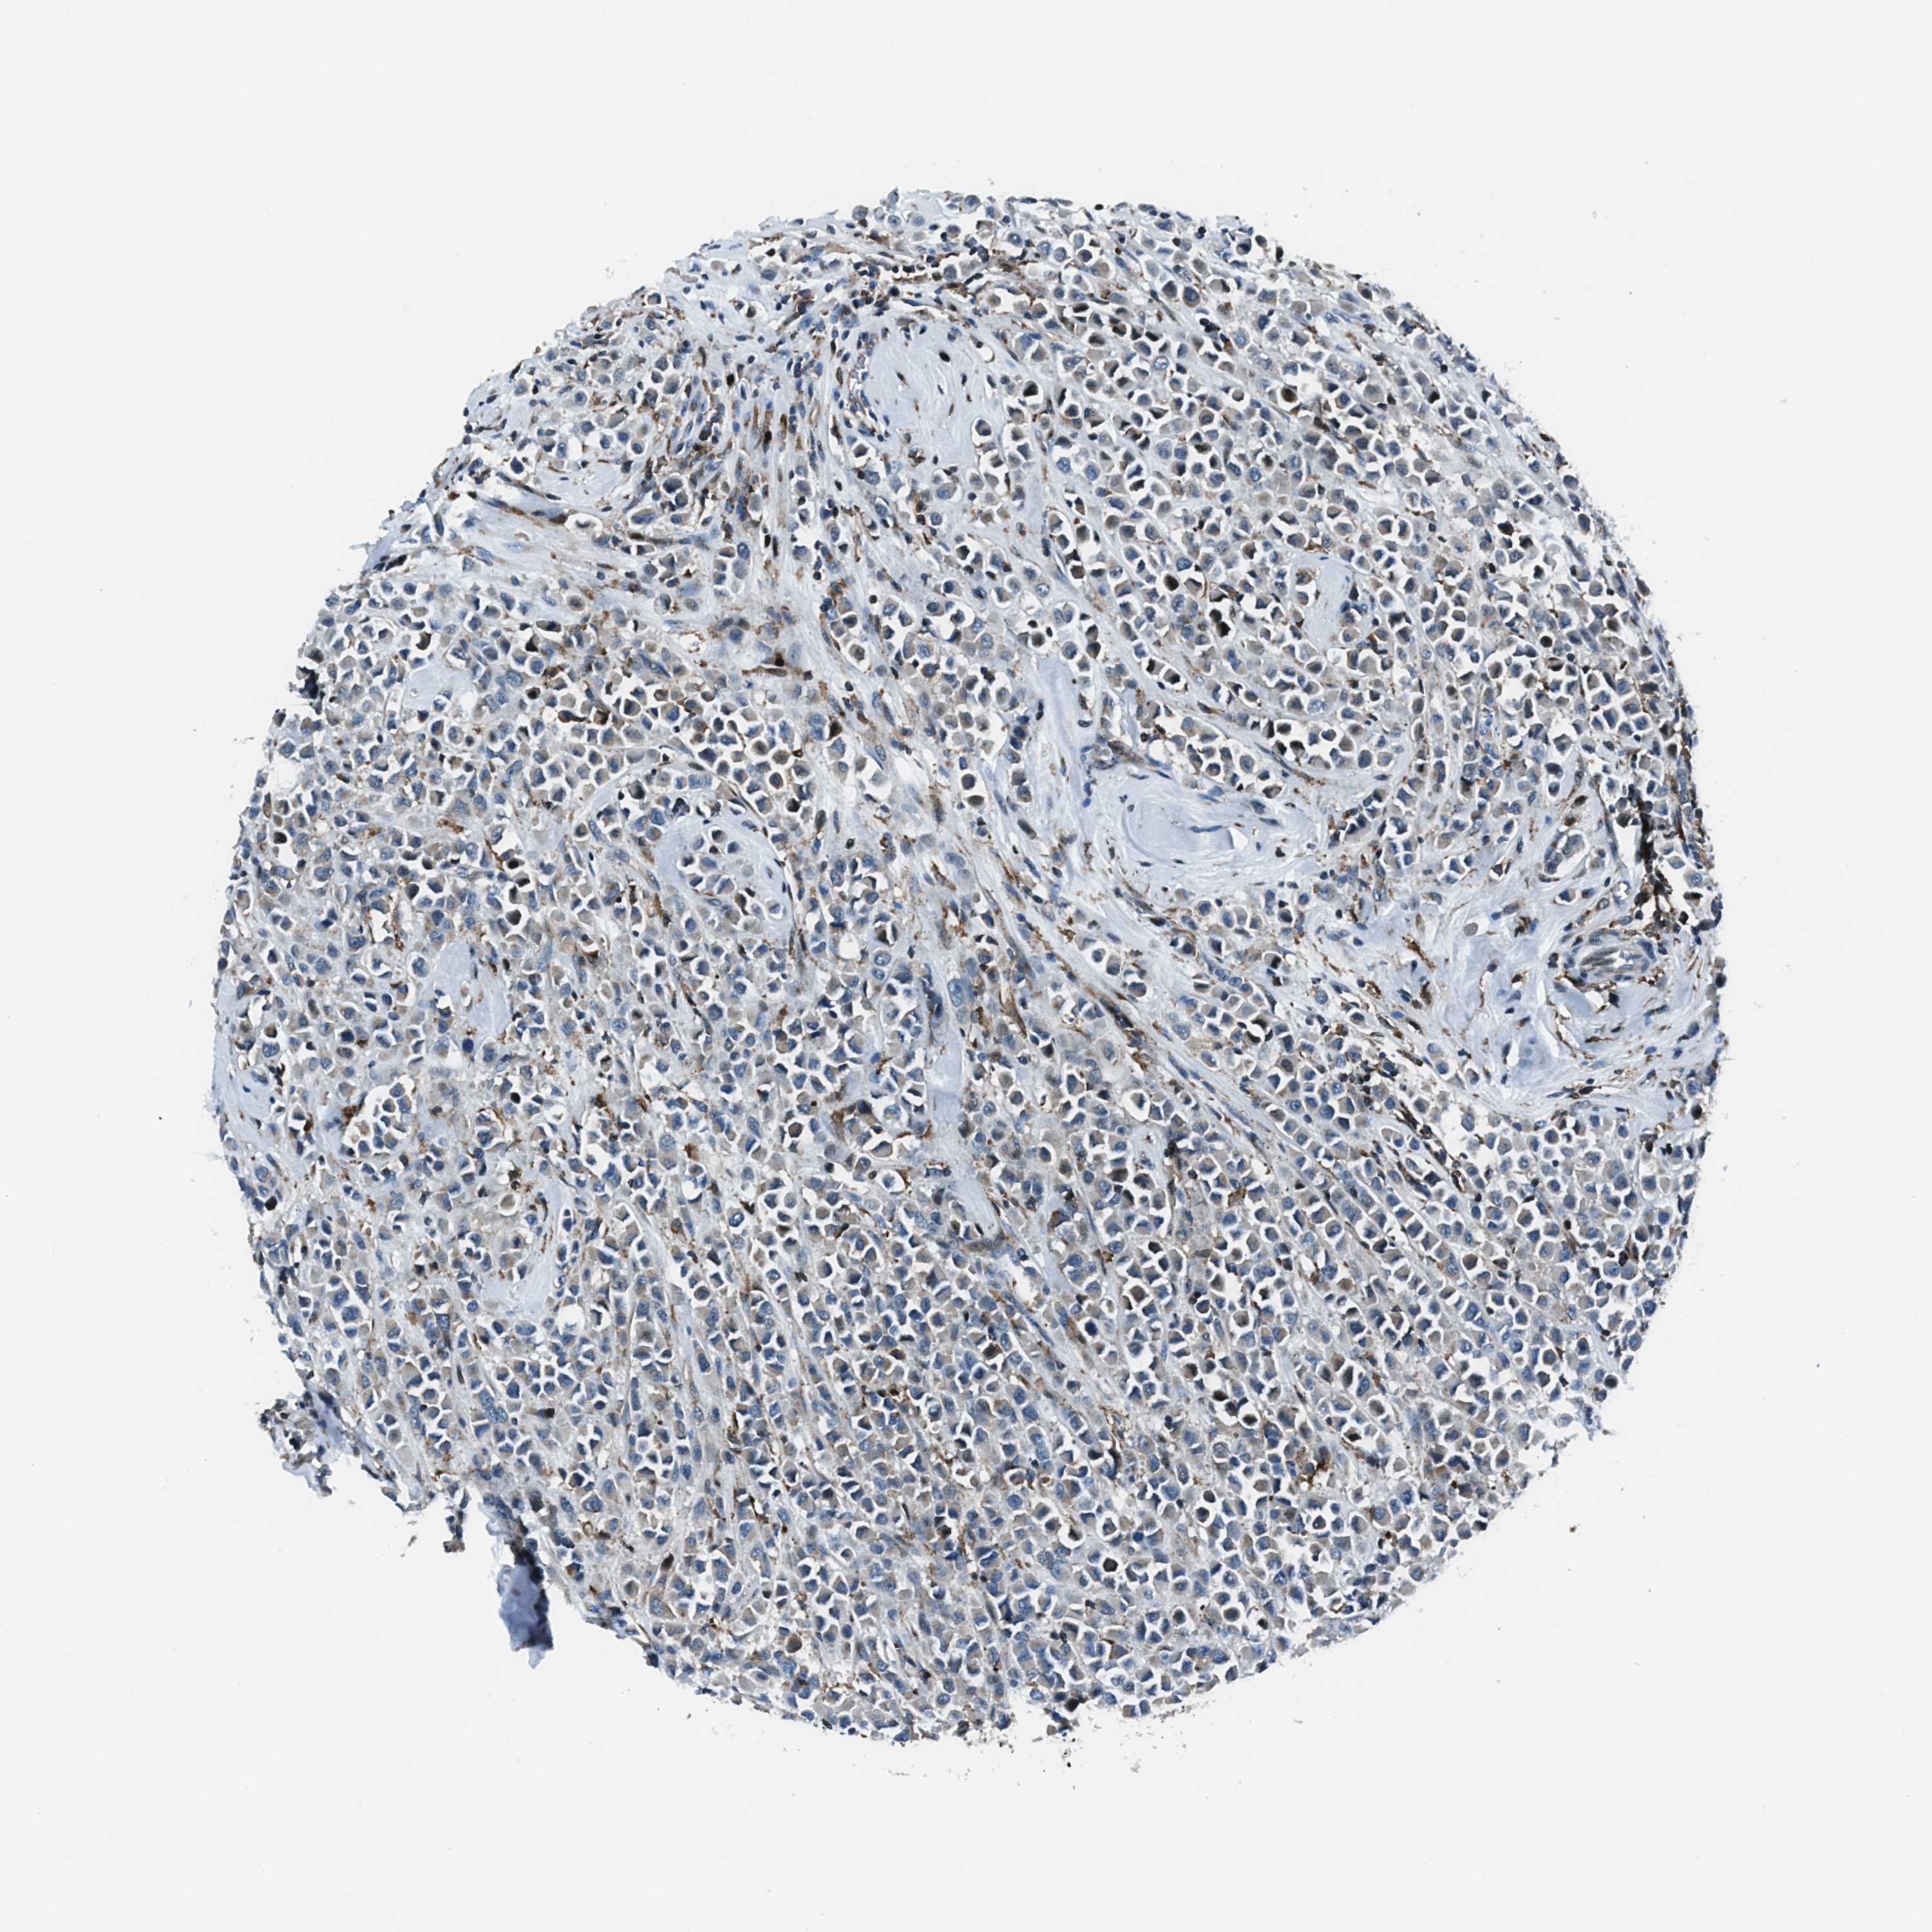

BRCA TCGA BRCA VALIDATION PROTEIN EXPRESSION